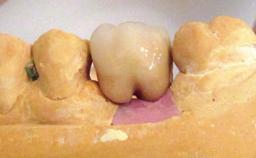

Peri-implant Carcinoma

Oral implants are highly successful and offer long-term benefits, especially in the rehabilitation of edentulous patients or patients with oral defects following ablative tumor surgery (Albrektsson and coworkers 1986), and also after radiation therapy (Schiegnitz and coworkers 2014). With the number of implants placed globally going into the millions, implant dentists have observed some rare adverse events. Although carcinogenesis around implants is an exceedingly rare phenomenon, we recently reported about 15 patients treated for carcinomas adjacent to implants at our clinical department over a period of fifteen years (Moergel and coworkers 2014). The following case represents a patient of this cohort; it discusses possible risk factors and makes suggestions for a recall schedule. A 70-year-old woman was referred to our outpatient department for evaluation of a rapidly growing macroscopic alteration of the mucosa in the left mandible.